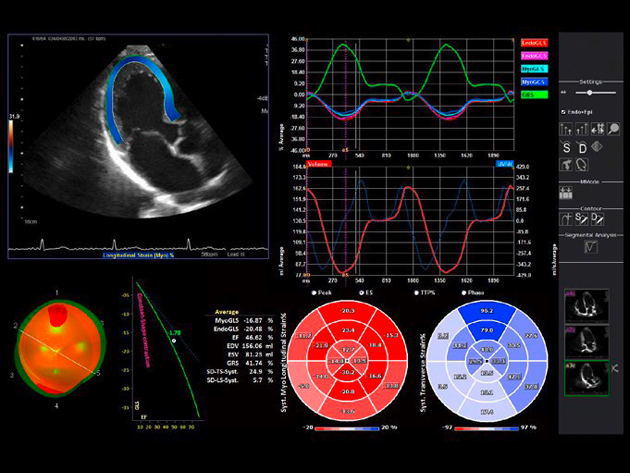

Απεικόνιση 1